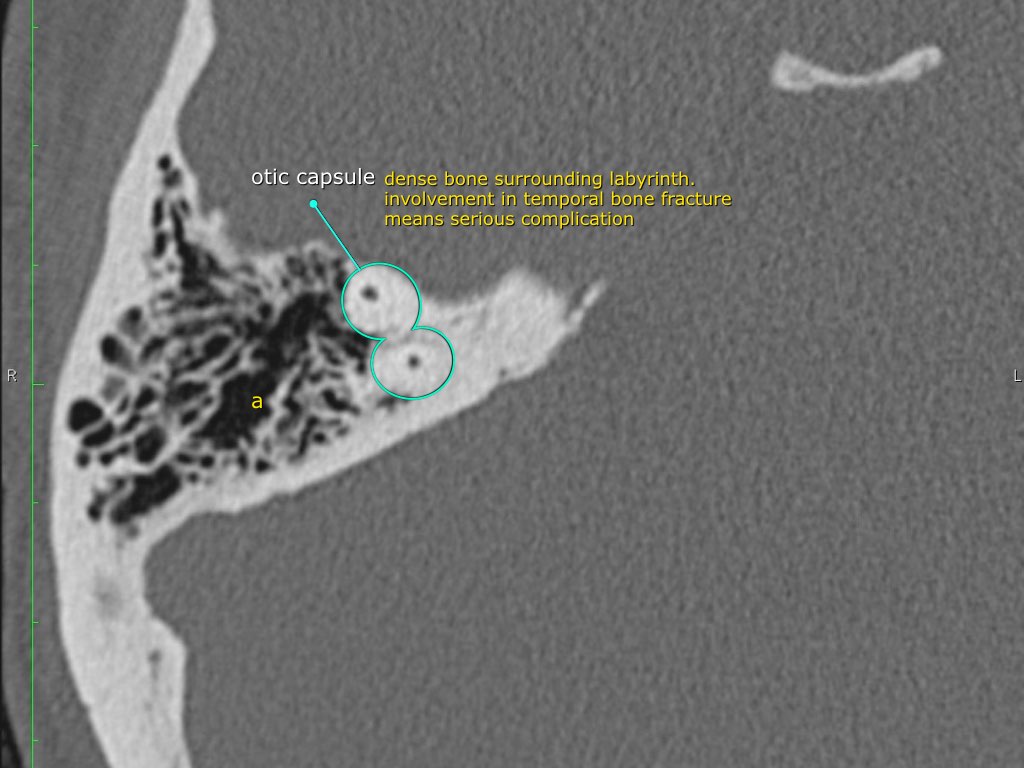

Trong bài tổng quan này, chúng tôi trình bày giải phẫu bình thường trên mặt phẳng cắt ngang (axial) và mặt phẳng cắt đứng ngang (coronal) của xương thái dương thông qua việc duyệt qua các hình ảnh.

Một số cấu trúc được thảo luận chi tiết hơn với trọng tâm là các bệnh lý liên quan.

Giải phẫu xương đá trên mặt phẳng cắt ngang (Axial)

Cuộn qua các hình ảnh.